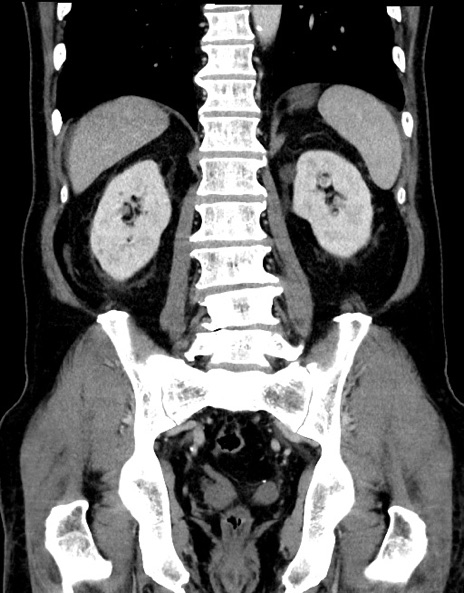

症例15(冠状断像)

【症例】70歳代男性

【主訴】腹痛

【現病歴】今朝から腹痛あり。全体的に痛い。特に左上の方。排ガスが今日はない。冷や汗が出る。

【既往歴】直腸癌術後

【身体所見】左側腹部〜上腹部に圧痛あり。腹膜刺激症状明らかなではない。軽度反跳痛。左下腹部に術後瘢痕あり。

【データ】WBC 7700、CRP 0.02